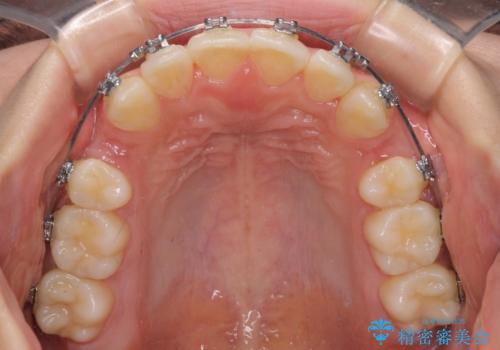

- メタルブラケット

- 治療期間

- 1年5ヶ月

上下左右4本抜歯する場合には、通常2年から2年半ほどの期間を要しますが、僅か1年半で終了することができました。